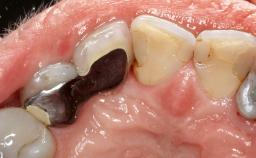

A 79-year-old female patient was referred to the Department of Periodontology of the University of Bern, Switzerland by her private dentist in May 2019. She had been rehabilitated in May 2005 with two tissue-level implants (Institut Straumann AG, Basel Switzerland) at sites 13 and 15, supporting a three-unit cemented fixed dental prosthesis (FDP). The metal-ceramic FDP had been cemented permanently with a glass-ionomer cement (Ketac Cem; 3M ESPE, Seefeld, Germany). Implant 13 had been diagnosed with peri-implant mucositis by the referring dentist in the course of regular supportive therapy. The patient was in good general health, did not smoke, and exhibited good self-performed plaque control.